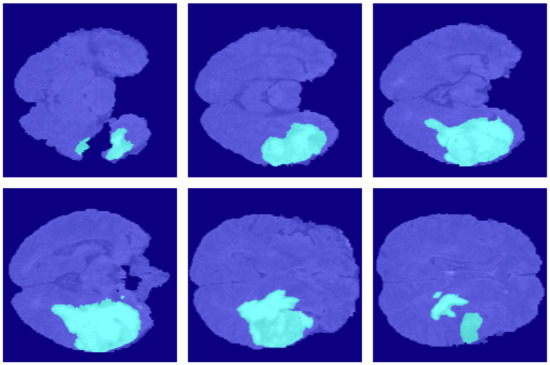

4.2. Segmentation Results

5.1. Ablation Experiment of Generative Mask Sub-Network